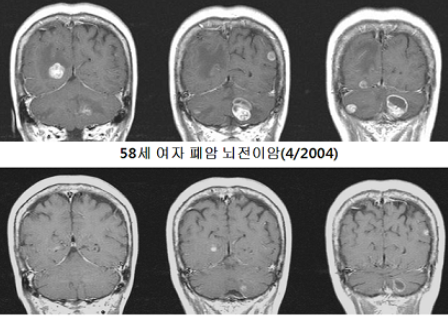

- 전이성(속칭 전이된) 뇌종양(Brain metastases): 몸의 다른 부위(폐·유방·피부(흑색종)·신장·대장 등)에서 발생한 암세포가 혈류나 림프로 뇌에 옮겨와 생긴 종양. 원발부위 암이 더 흔합니다.

전이성 병변은 원발암의 특성을 많이 반영합니다. 대부분의 뇌전이는 폐암·유방암·멜라노마(흑색종)·신장암·대장암 등에서 옵니다. 뇌전이는 보통 여러 개(다발성)로 나타나는 경우가 많고, 증상·치료 전략이 원발암 치료와 연계됩니다

- 전통적 방사선과 더불어 정위적 방사선수술(SRS, 감마나이프·사이버나이프 등)이 소형·다발 병변에 효과적입니다. 전이성 뇌종양 치료에서 널리 사용됩니다.